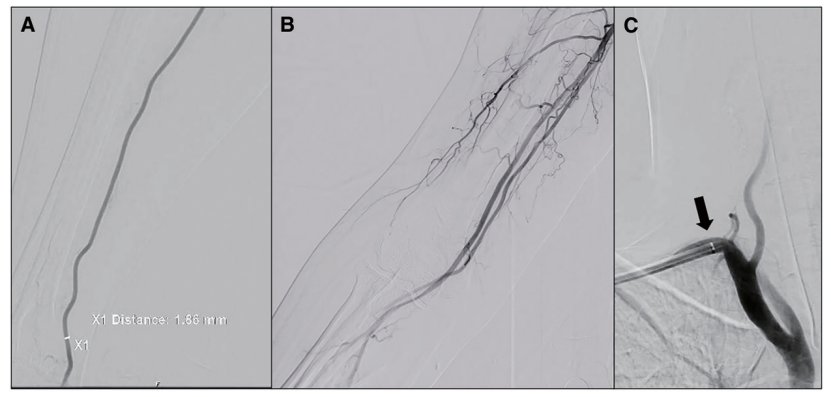

我们将4F鞘(Medikit, Tokyo, Japan)置入右侧桡动脉。我们在直径为1.86mm血管进行了一次的后侧血管穿刺术。我们确认尺动脉到远端有足够的回流。桡动脉分叉发生在肱部区而非肘部(图2A和2B)。

我们交换置入6F Axcelguide(Medikit),没有进行任何动脉内扩张剂注射。我们在置入时没有检测到阻力,只有在引导到右侧锁骨下动脉的椎动脉起始处附近才出现阻力(图2C)。

图2:桡动脉造影(A,B)和锁骨下动脉造影(C)。(A)穿刺部位血管直径1.86mm。(B)桡动脉在肱动脉区域分叉。(C)6F Axcelguide(Medikit)引导至椎动脉起始处附近(箭头)。